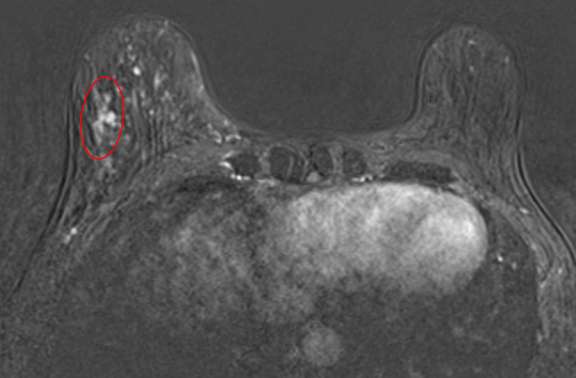

Biopsy-Proven Microinvasive Ductal Carcinoma as Linear, Clumped NME

Figure 3. Biopsy-Proven Microinvasive Ductal Carcinoma as Linear, Clumped NME Contrast-enhanced breast MRI, axial subtraction image demonstrates right breast NME with linear distribution and clumped internal enhancement spanning 20 mm at 7 o’clock, consis